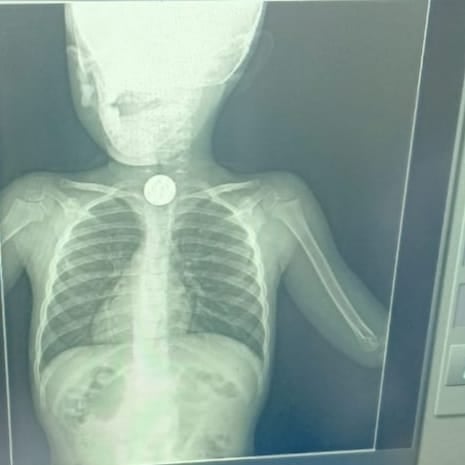

تمكنت الفرق الطبية في قسم منتظير الكبد والجهاز الهضمي في مستشفى أبو كبير المركزي في محافظة الشرقية، من إنقاذ حياة طفل؛ بعدما ابتلع عملة معدنية.

استقبل قسم مناظير الكبد والجهاز الهضمي بمستشفى أبو كبير المركزي طفل يبلغ من العمر 5 سنوات، يعاني من صعوبة في البلع والتنفس؛ نتيجة ابتلاع عملة معدنية أدت إلى انسداد مجرى الطعام.

على الفور تم التحضير لمنظار علوي طوارئ، وقام الفريق الطبي بقسم المناظير بمشاركة الدكتور عبدالمنعم زناتي، والدكتور صهيب إبراهيم، والدكتور عبدالستار محمد، والدكتور أسماء رزق، بالإضافة للدكتورة أسماء السيد استشاري التخدير.

وتمكن الفريق الطبي من استخراج العملة المعدنية من مرئ الطفل، وتم خروج الحالة من المستشفى بصحة جيدة.